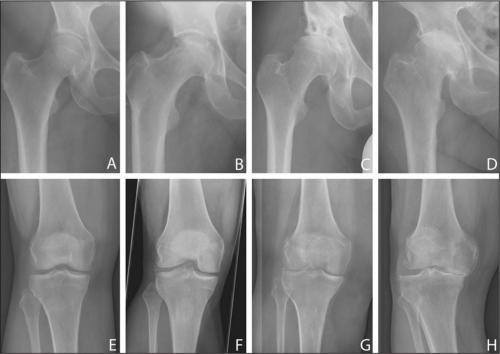

Вид на поражённую хрящевую поверхность.

Стадии артроза коленного сустава. Обратите внимание на сужение суставной щели.